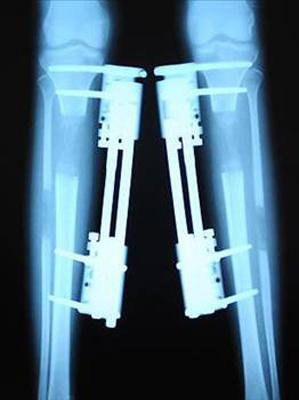

DİSTRAKSİYON OSTEOJENEZ

Boy sorunu yaşayanlar apartman topuklu ayakkabılar giymek gibi yöntemlere başvurabilir. Diğer yandan, bacaklarınızın kırılmasını da tercih edebilirsiniz. Sovyet doktor Gavriil Ilizarov'un 1950’lerde keşfettiği distraksiyon osteojenez yönteminde, kırılan kemik metal desteklerle geriliyor. Ardından, kemiğin uçlarından gelişen yeni kemik dokusu boşluğu kapıyor. Bu esnada metal destekler kırığı daha fazla ayırmak için sürekli olarak geriliyor. Bu döngü ve germe yöntemi istenilen kemik uzunluğuna erişilene dek sürüyor. Bu yöntem, genelde sakat doğumlarda kullanılıyor.